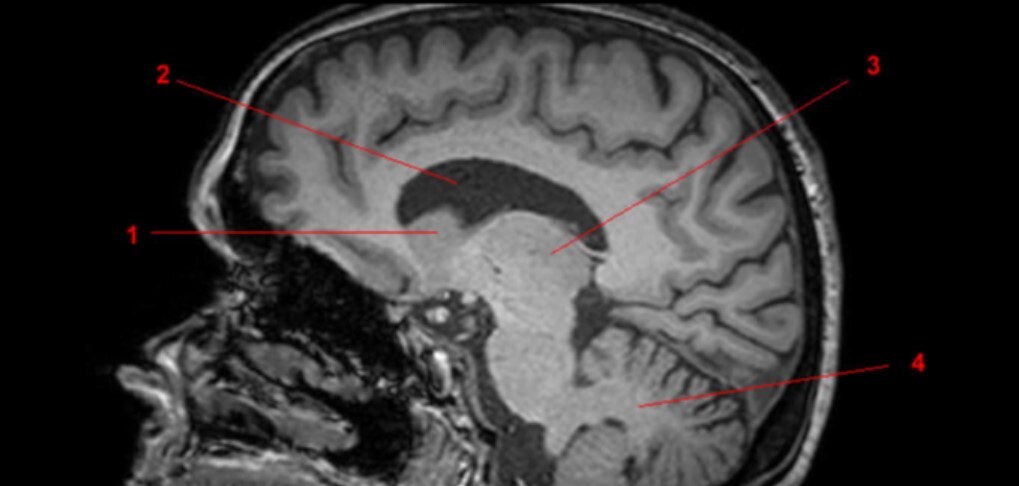

14

Q

Label 1-9

A

1=Rostrum (CC)

2-Genu (CC)

3-Body (CC)

4=Splenium (CC)

5=Lateral ventricle

6=Thalamus

7=Midbrain

8=Pons

9-Medulla oblongata

15

Label 10-18

10-4th ventricle

11=Cerebellum

12=Cisterna Magna

13=Basilar artery

14=Clivus

15-Mamillary body

16=Optic chiasm

17=Infundibulum

18=Occipital bone

16

Label 19-27

19=Sphenoid sinus

20=Quadrigeminal cistern

21=Occipital lobe

22-Frontal lobe

23-Parietal lobe

25-Cerebral aqueduct

26-Frontal bone

27-Spinal canal